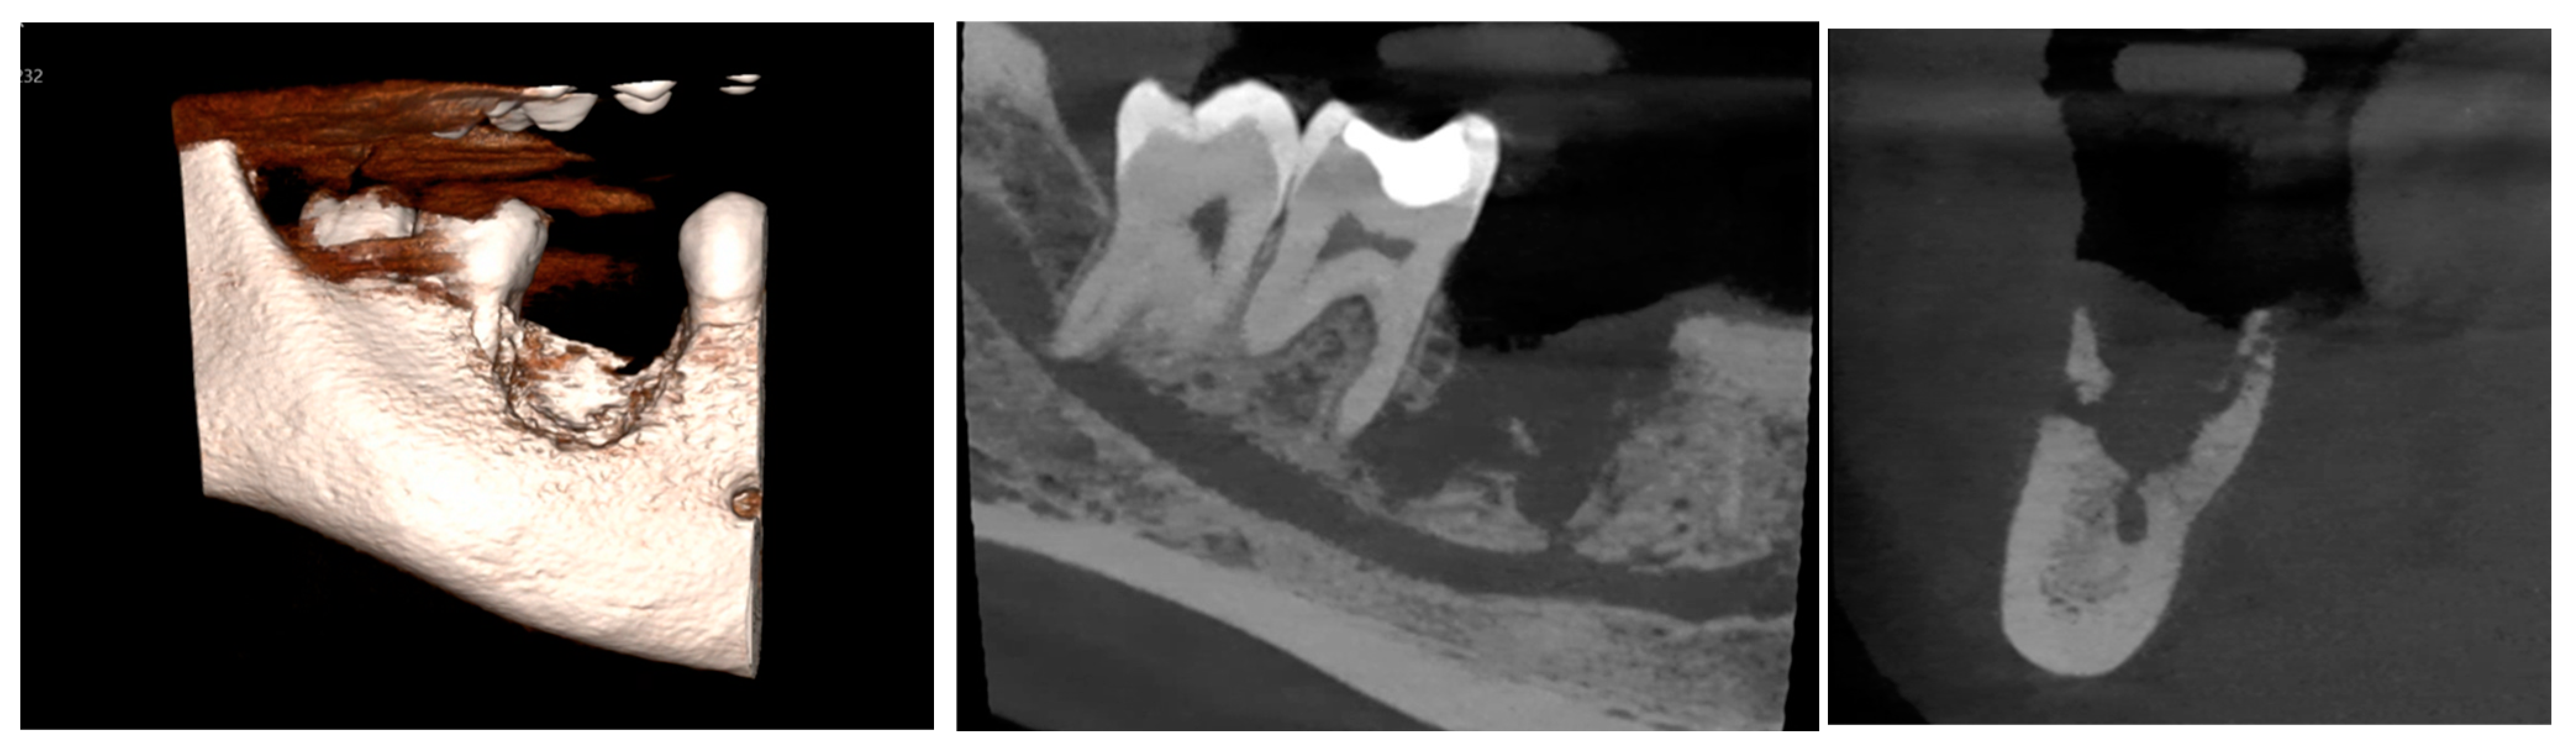

2. Case Presentation

2.1. Clinical Examination

2.2. Differential Diagnosis

2.3. Management and Intervention